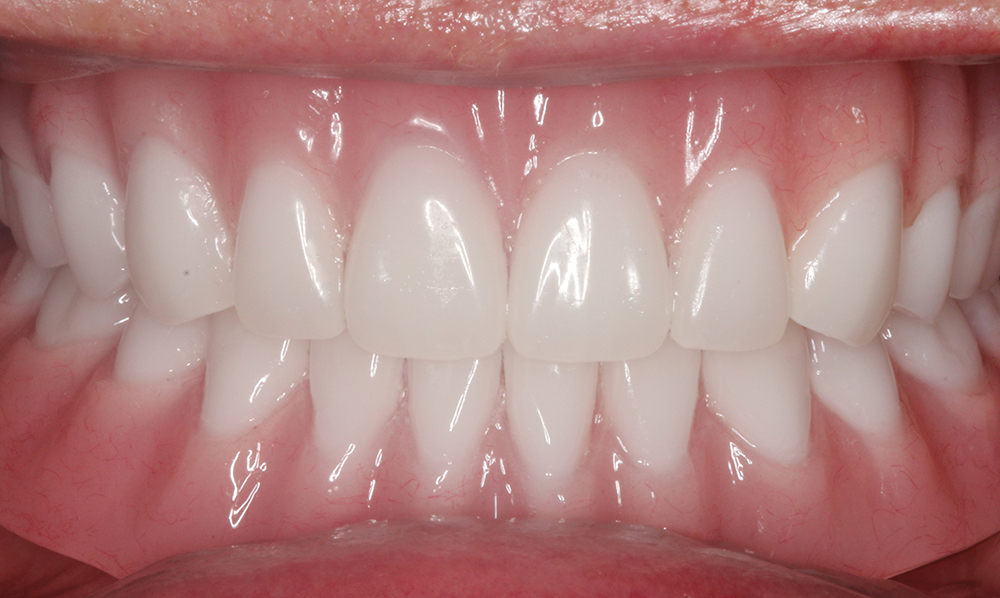

The following case report illustrates a straightforward clinical workflow for delivering a Locator® Overdenture (Glidewell; Newport Beach, Calif.) — a removable appliance that seats over Locator Abutments connected to the implants. Denture caps are embedded in the overdenture and provide retention by seating over and engaging the Locator Abutments. By stabilizing the prosthesis, these retentive devices improve function and chewing efficiency.

Our patient is a middle-aged female who presented with a chief complaint of ill-fitting, unstable maxillary and mandibular conventional dentures. We discussed several options, including relining her existing dentures, fabrication of new conventional dentures, implant-retained overdentures and fixed implant-supported prostheses. The patient opted for implant placement and restoration with a Locator Overdenture — which would provide an effective, economical means of addressing the patient’s needs and improving prosthetic stability and dental function.